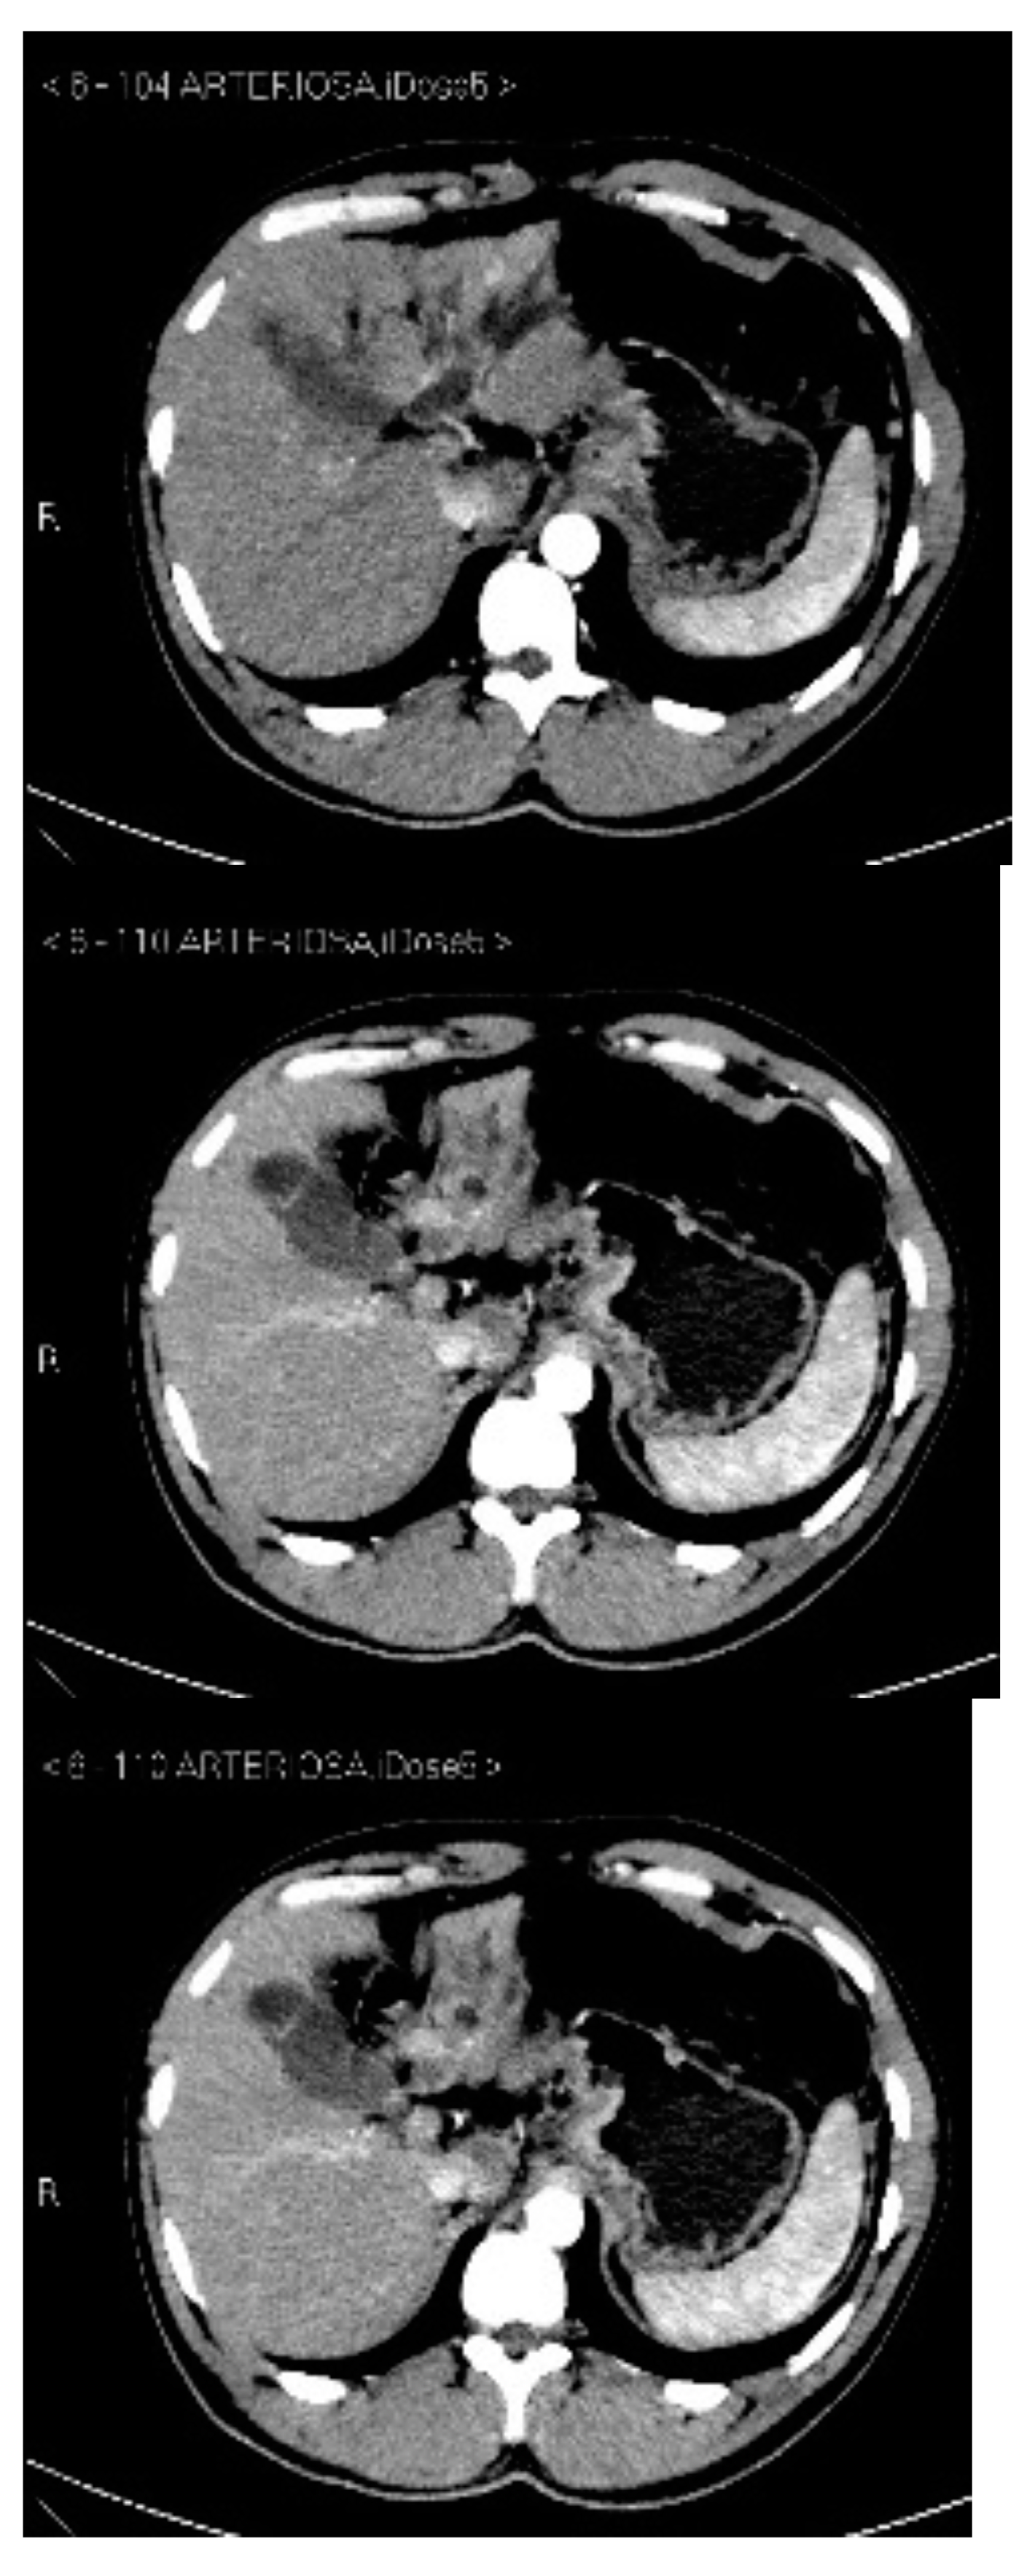

Subsequently, an upper-abdomen Computed Tomography (CT) scan and liver Magnetic Resonance Imaging (MRI) were performed (Figure 1, Figure 2, Figure 3, Figure 4, Figure 5, Figure 6 and Figure 7).

Figure 4.

MRI T1, T1 in, T1 out, and DWI.

A mass of 1.8 cm was detected within the biliary branch for the third hepatic segment, characterized by nodular impregnation in the arterial phase and irregular and partial washout in the portal venous phase. These findings were compatible with a heterologous lesion, although it was not possible to perform a diagnosis among HCC, intrahepatic CCA or other pathological lesions.